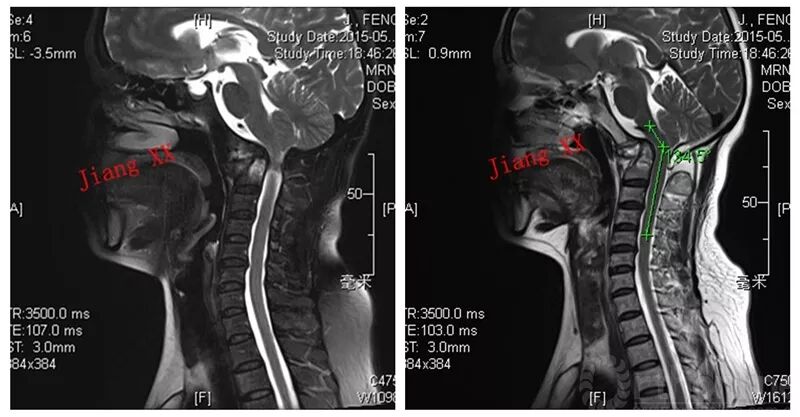

寰枢椎半脱位

寰椎前弓骨折并环枢椎侧脱位

new0263:寰枢外侧关节半脱位

病例一:患者女性,49岁,因颈部活动受限4月入院,诊断为寰枢椎脱位,颅底